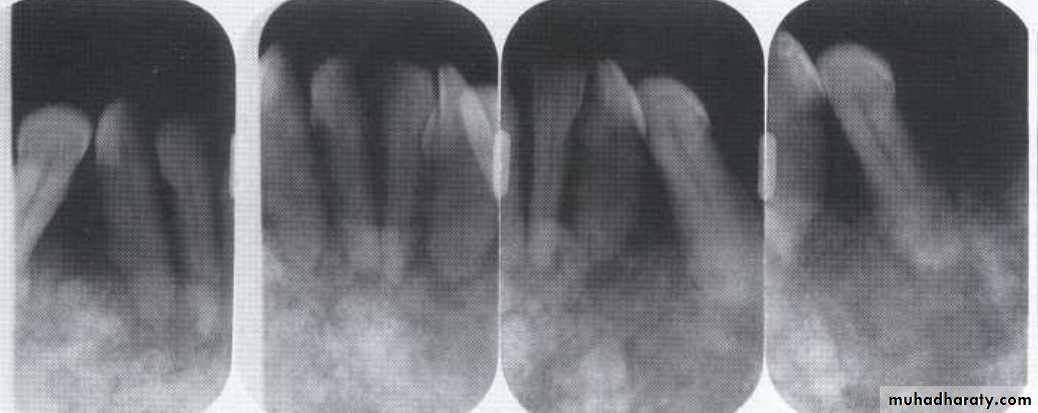

Radiographic features:* Soft tissue inflammation→no change. Location: Most common site → mand 3rd molar region.

*In close proximity to bone or inside follicular space.

*Radiolucency or sclerotic with thick trabeculae.

Periphery: ill defined with gradual merging with sclerotic region.Internal structure: *Sclerotic with thick trabeculae. Or radiolucency adjacent to crown.

Effect on surrounding structures:*Sclerosis and rarefaction of surrounding bone.

*In extensive cases, new bone formation at inferior cortex, posterior border of the ramus, and

along the coronoid notch.